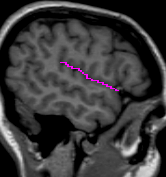

The brain lobe borders are determined by drawing sulci lines in the sagittal

and axial views.

The insular cortex is “hidden” between the temporal and inferior parietal corticies. By drawing sulci lines in the sagittal view, we gain an outline of it in the coronal. Choose a sagittal slice where insula is clearly visible (Fig 1), then draw a “circle” around it (Fig 2). Do this for several slices and for both hemispheres.

Figure 1              Figure

2